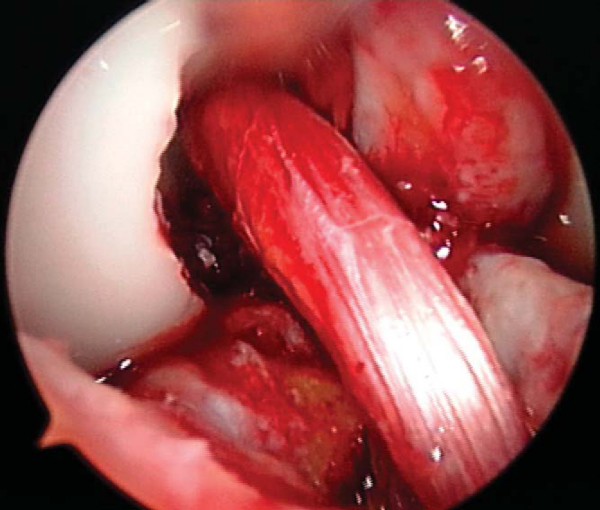

6. Graft Placement and Fixation

In the push-in technique, the graft is advanced through the tibial tunnel into the joint by use of a two-pronged pusher at the base of the femoral plug (

Fig. 60-9A

). A hemostat is placed through the inferomedial portal, grasping the femoral bone plug at the junction of the proximal and middle thirds. With the cortical surface of the femoral plug oriented posteriorly, the hemostat is used to guide the femoral plug into the femoral tunnel (

Fig. 60-9B

).

In the pull-through technique, the femoral bone plug suture is threaded through the eye of the Beath pin and retrieved proximally by pulling the Beath pin from its exit site in the thigh. The sutures of the femoral bone plug and the tibial bone plug are held taught as the graft is pulled through the knee. A probe or hemostat can be used to ensure proper orientation of the femoral bone plug as it enters the femoral tunnel.

Once the femoral bone plug is completely seated in the femoral tunnel, a nitinol guide pin (Linvatec, Largo, Fla) is placed into the femoral tunnel at the 11-o’clock position of the graft. The knee is flexed to 110 to 120 degrees, allowing easier passage of the guide pin within the femoral tunnel. The pin should be introduced without resistance; otherwise pin divergence should be suspected. A satellite pusher can be used to seat the femoral bone plug as needed. The tibial bone plug should be evaluated at this time for graft-tunnel mismatch. If the tibial plug is overhanging from the tibial tunnel, the graft can be removed and the femoral tunnel further recessed.

Femoral graft fixation is performed with an interference screw placed over the nitinol guide wire with the knee hyperflexed. The screw should be placed against the cancellous surface of the bone plug, away from the tendon insertion, to diminish the risk of graft injury or laceration. While tension is held on the tibial plug sutures, the knee is brought from 100 degrees to full extension to cycle the graft to ensure minimal graft motion as well as to assess impingement.

At this time, the tibial bone plug is externally rotated 180 degrees (toward the lateral side). This maneuver allows the tibial screw to be placed along the cortical surface and anterior. This screw placement avoids possible damage to the graft by a posteriorly placed screw with the knee in flexion as well as limits impingement that may occur with an anteriorized graft and a posteriorly placed screw.

The knee is placed in full extension, tension is held firmly on the tibial sutures, a nitinol wire is placed anterior to the tibial plug, and the interference screw is advanced and seated just below the cortical surface of the tibia. At this time, the arthroscope is placed into the knee, the ACL is visualized and probed to ensure proper tension, and a Lachman test and pivot shift test are performed (

Fig. 60-10